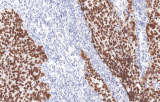

Apoyo al diagnóstico diferencial

Los paneles de IHQ permiten diferenciar entre mimetizadores benignos, tumores GU primarios y malignidades metastásicas mediante el resaltado de linaje celular y antígenos tumorales específicos.

Integración en la oncología moderna guiada por biomarcadores

La literatura reciente destaca el papel creciente de la IHQ como sustituto del perfilado molecular y el descubrimiento de biomarcadores, particularmente en la subtipificación del cáncer de vejiga y próstata.